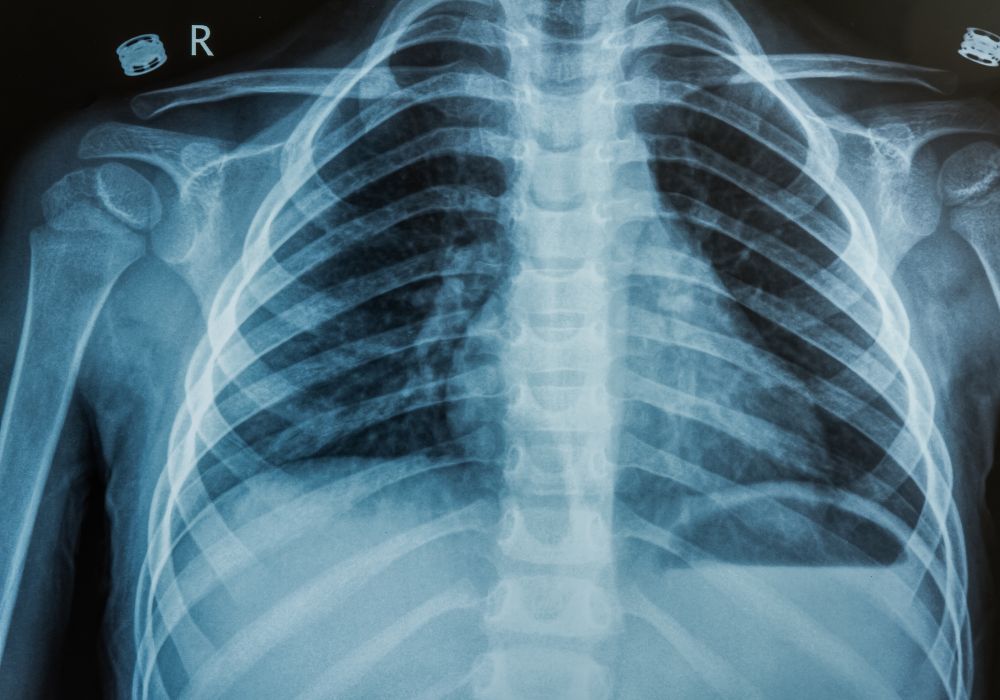

Optimize Chest XRay Documentation and Coding StreamlineMD What Can A Chest X Ray Diagnose Abnormalities of ribs such as fractures, bone lesions and masses. Pulmonary screening and diagnostics biopsies. Some of these symptoms include:. See if your pacemaker, defibrillator, or other heart. Look at your chest bones, heart, and lungs; A bad or persistent cough. What Can A Chest X Ray Diagnose.